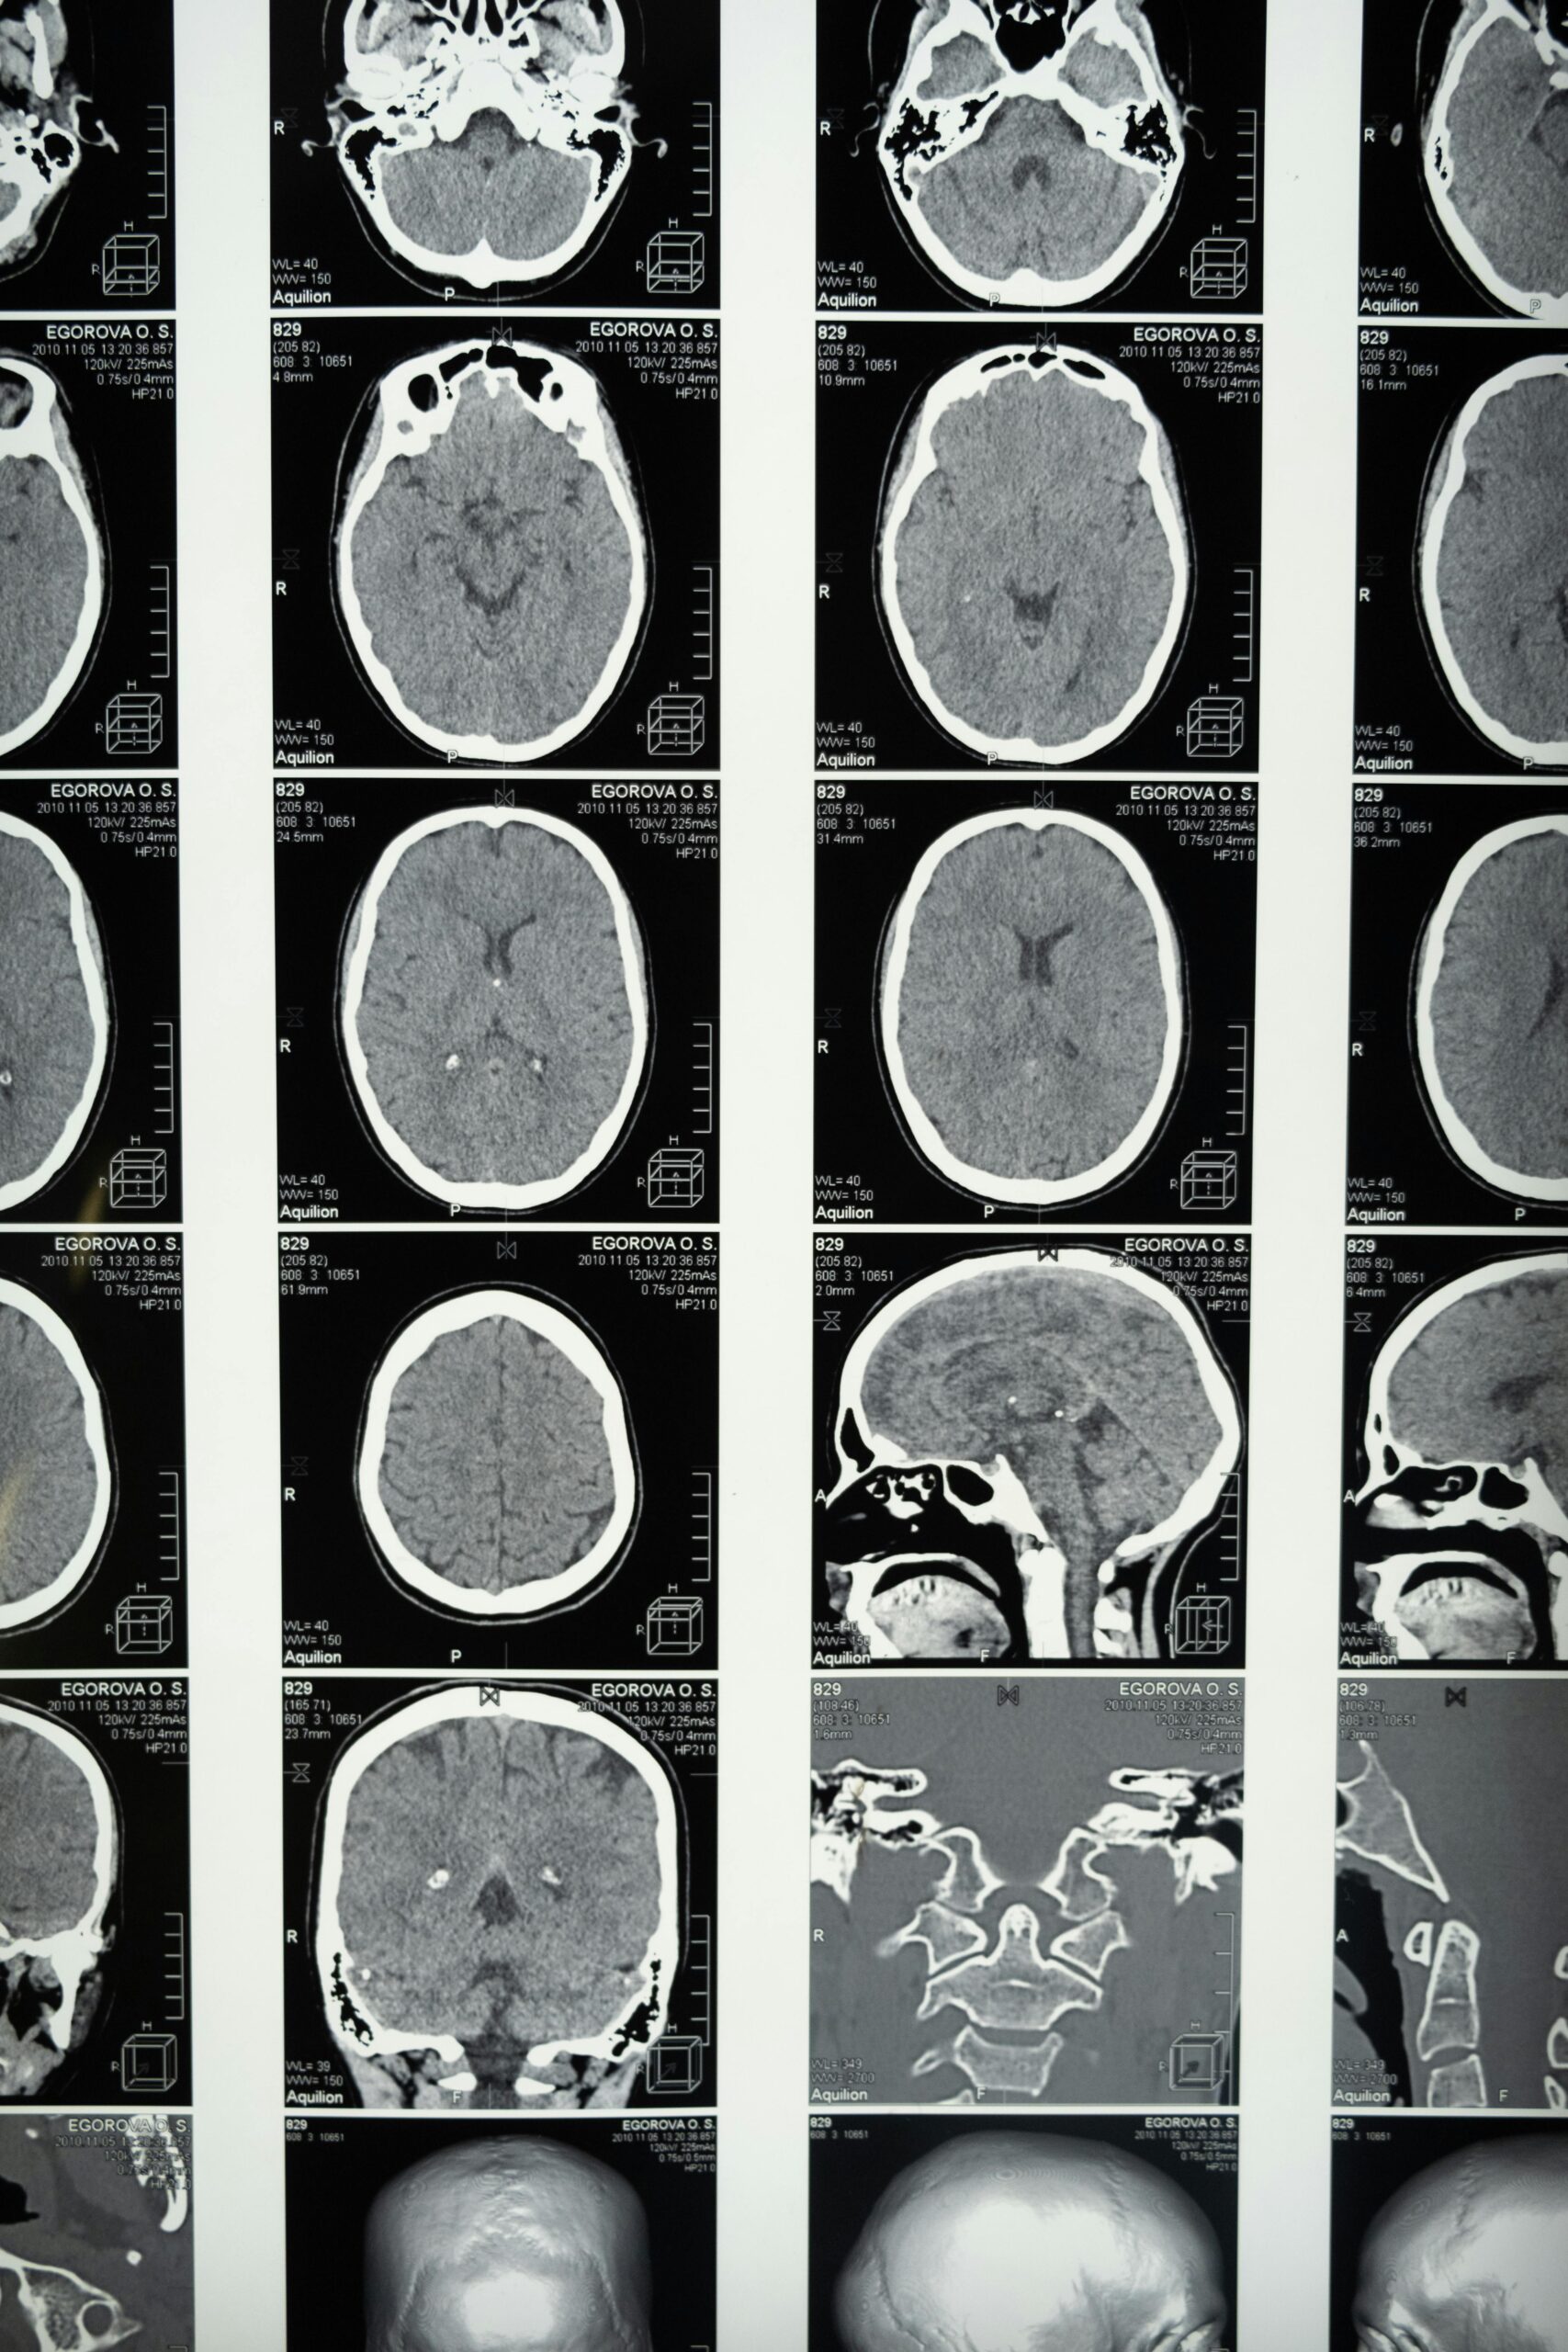

Radiology